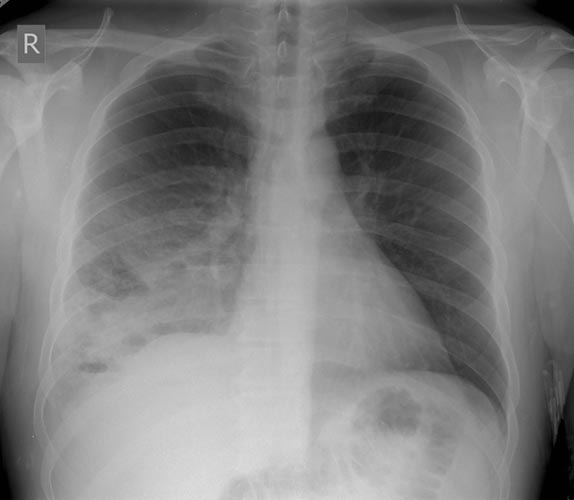

A previously healthy 43-year-old male presented with cough, fevers, and leukocytosis. A chest radiograph (Figure 1) revealed extensive consolidation in the right lower lung containing multiple cavities with air-fluid levels consistent with a necrotizing infection. A chest computed tomogram (Figure 2) showed an abscess cavity and consolidation in the right lower lobe with an aberrant blood supply from the descending aorta. This systemic blood supply was confirmed by subsequent 3D reconstruction (Figure 3). He was initially treated with IV antibiotics, resulting in normalization of his temperature and white blood cell count. He was then discharged home on a 3-week course of oral antibiotics. Three days prior to a planned surgical resection, he underwent angiographic localization of the feeding artery (Figure 4) and coil embolization (Figure 5).